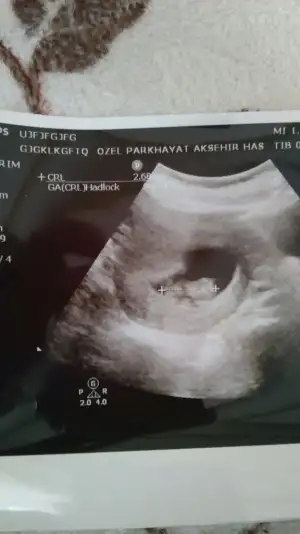

Boyle bi goruntusu var teyzeleri icimden kiz geciyor ama doktor bu goruntu kizda da boyle erkekte de boyle gorunur dedi 10 gun sonra bakalim tekrar cinsiyet icin dedi